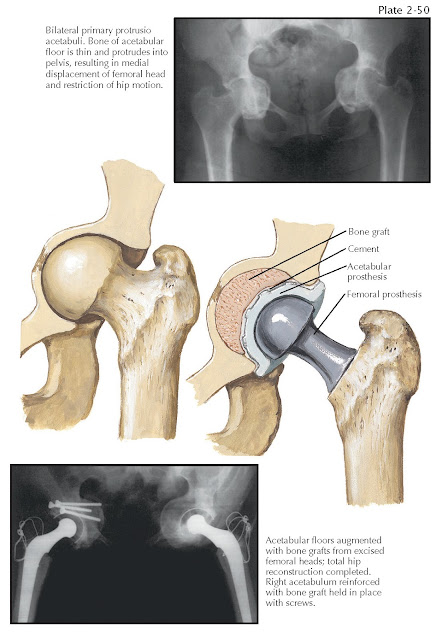

PROTRUSIO ACETABULI

As a result of any disease that causes bone resorption, the pelvic bones

become osteoporotic and soft and the medial wall of the acetabulum may be

gradually displaced medially. Bone remodeling in response to applied load

causes varying degrees of superomedial protrusion of the femoral head (see Plate 2-50). Protrusio

acetabuli occurs when the femoral head is displaced past the ilioischial line

in the pelvis. Other conditions that can cause progressive protrusion of the

acetabulum are osteomalacia, rickets, Paget disease of bone, and infections.

Central dislocation of the femur due to trauma can also heal with a protrusion

deformity. Arthrokatadysis (Otto pelvis) is a rare idiopathic form of severe

bilateral protrusio acetabuli most often seen in adolescent females. Metastatic

carcinoma to the pelvis can lead to pathologic fractures, which result in a

protrusion deformity.

Treatment. Like medial wall defects, protrusio

acetabuli is treated with various types of bone grafts to reinforce areas

deficient in bone mass to ensure that prosthetic

components remain in the correct anatomic positions.

If there is enough anterior and posterior wall remaining, a cementless

socket is impacted in place with cancellous bone graft behind it. If severe

deficiencies are present, an antiprotrusio cage may be placed over the top of

the cementless socket. This cage rests on the ilium and ischium, thereby

transferring the load from the hip to the intact

pelvis.